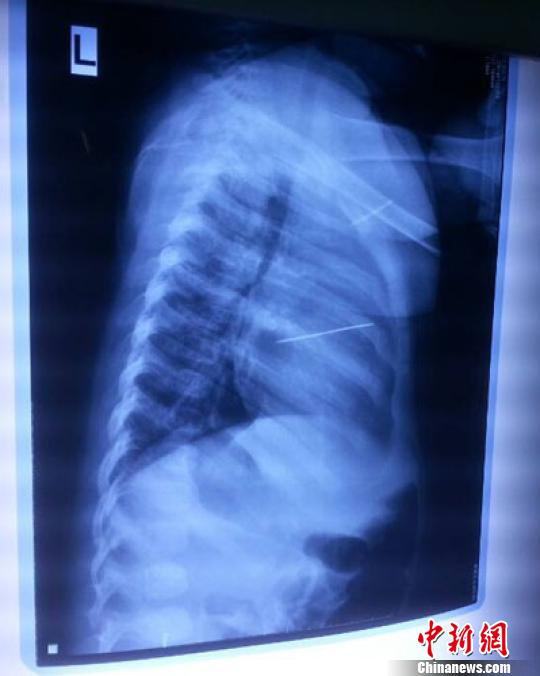

女嬰胸片提示心臟里面扎了一個(gè)縫衣針 蔡迅翔 攝

醫(yī)院胸心外科主任翟波介紹說,1月22日,小患者彤彤因?yàn)榘l(fā)燒抽搐來醫(yī)院就診,常規(guī)檢查時(shí)發(fā)現(xiàn)孩子心臟里面扎了一個(gè)縫衣針。

“第二天上午,我們做了個(gè)緊急彩超檢查,發(fā)現(xiàn)針是從患者右心室表面刺入,穿破室間隔,到達(dá)左心房,中間還有一部分損害到二尖瓣。于23號(hào)下午,我們就做了一個(gè)緊急手術(shù),手術(shù)中發(fā)現(xiàn),這枚針已經(jīng)刺入心臟,沒入了右心室的下面,表面已經(jīng)看不到針了,僅能看到一個(gè)小針眼,還在往外滲血,一點(diǎn)一點(diǎn)的滲,心包腔里面大概有100多毫升的出血,心包上一個(gè)洞,針在右心室表面刺入以后,穿過室間隔,在二尖瓣的上方,進(jìn)入了左心房,在針的四周,有很多纖維沉積物,包繞著這枚針。”翟波說,他們把針取出來以后,測量了一下,長度大概是五厘米,同時(shí)發(fā)現(xiàn)這個(gè)針給患者左心房的后壁造成了一定的損傷,左心房的后壁已經(jīng)損傷了三分之二,還剩下有左心房的外膜,很薄的一層,如果這一層再破的話,這個(gè)孩子將會(huì)引起大出血,很快就會(huì)死亡。